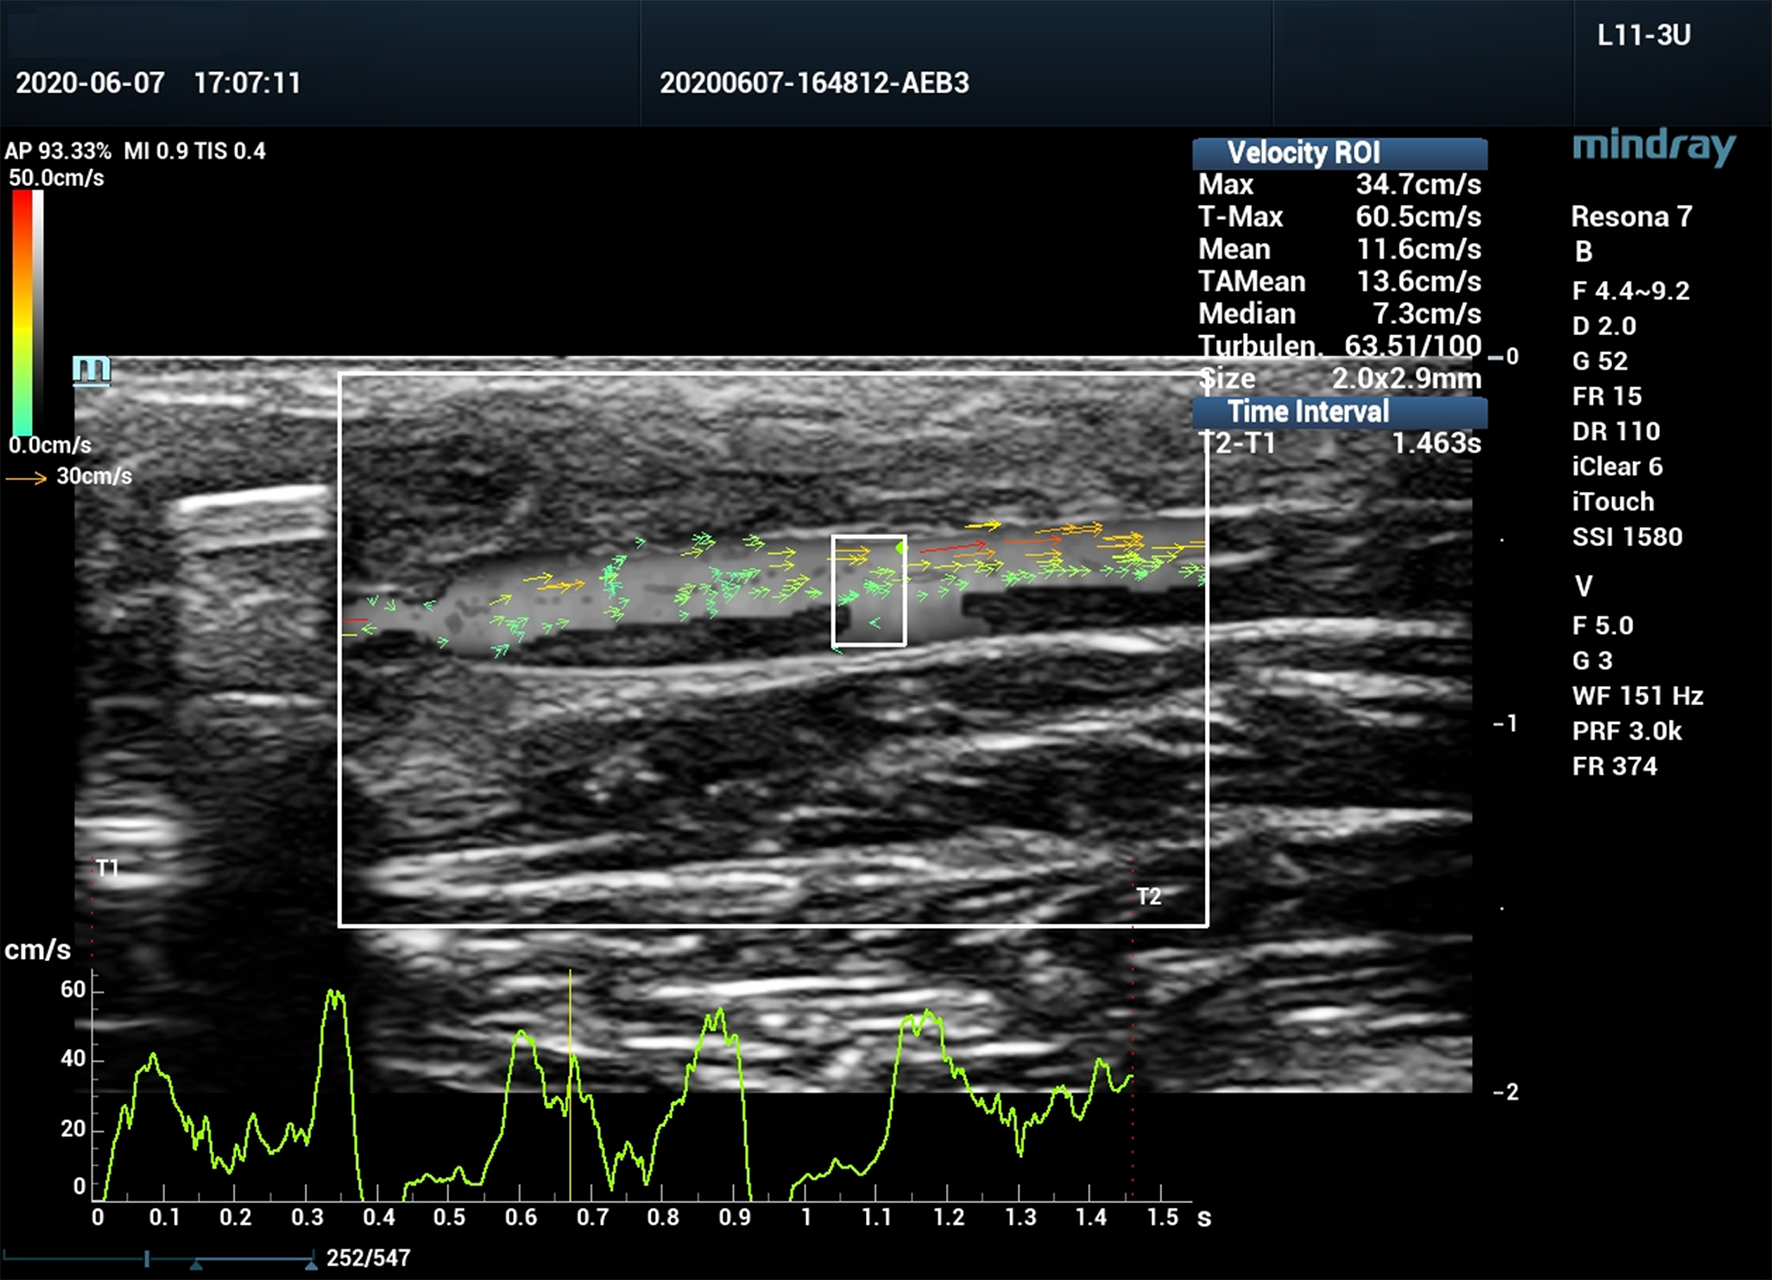

Figure 2

Vector flow imaging (V Flow) of a canine femoral artery.

All ultrasound assessments were performed with a Mindray Resona 7 ultrasound system (Shenzhen Mindray Bio-Medical Electronics Co., Ltd., Shenzhen, China). A 3-11 MHz linear array transducer (L11-3U) was used for the examination. The ultrasound system was equipped with V Flow mode, and is capable of obtaining blood flow turbulence index (Tur) at regions of interest (ROI). V Flow uses a series of arrows to represent blood flow direction and velocity. The arrow orientation indicates the direction of blood flow, and the arrow length and color represent the flow velocity. The longer the arrow, the higher the velocity. The range of velocities from high to low are expressed by colors from red to orange, to yellow, and to green (Figure 2). Tur indices were calculated by the ultrasound system using the following equation:

Where

N: number of velocity measuring points in the ROI, θi: flow velocity angle at ith measuring point, and Tur indices ranged from 0 to 1 (0–100%), 0 indicates pure laminar flow which means that all flow directions are exactly the same. The bigger the Tur is, the more turbulent the flow is (11).